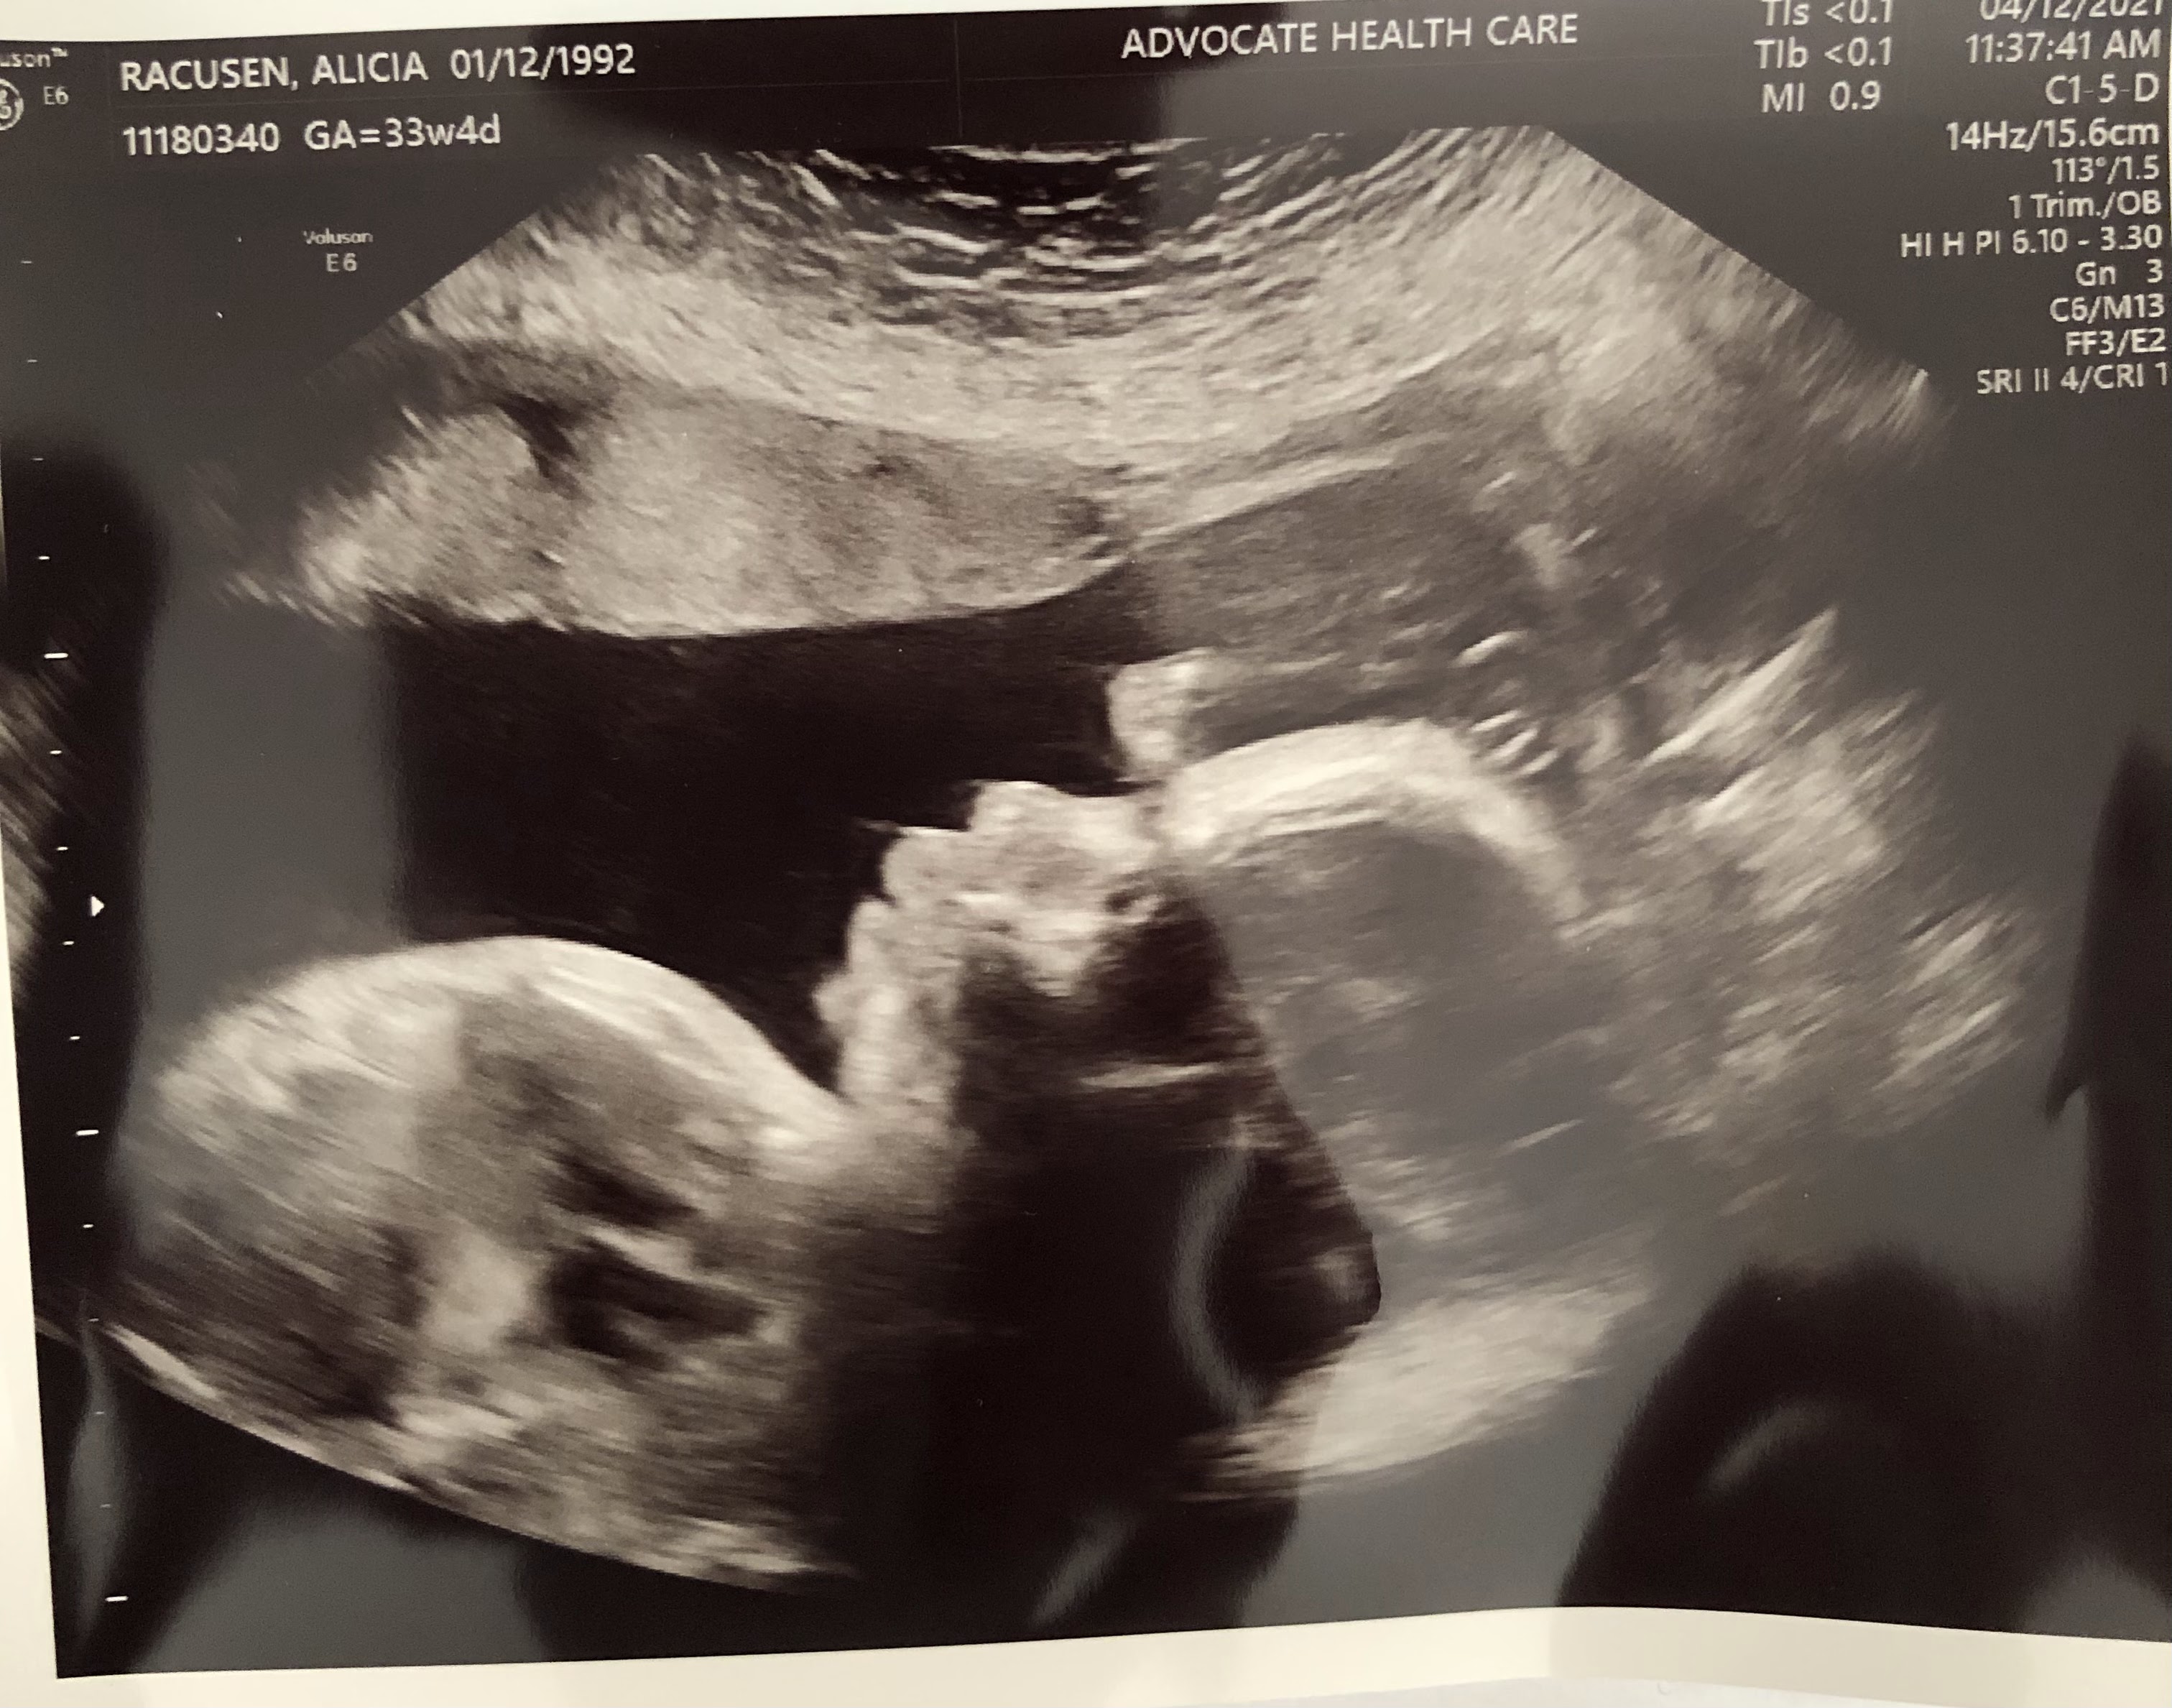

A 3D of our sweet sweet Winnie

We had our second fetal echo and medical meeting last Friday. I wish I could be giving better news but we were overwhelmed with so much new information that we are still trying to digest. I will try my best to convey what we learned. Winnie's heart is more complex than we thought. She still has the thicker walls on the right ventricle, hole, and a narrowing aortic valve. The hole is causing oxygenated and deoxygenated blood to mix, not making it to its proper channels and the narrowing of her valve will cause turbulence for the blood getting to the lungs. If we decide to intervene after birth she would would have to be taken to the NICU immediately and started on an intensive medication through an IV to try and get the blood to go where its supposed to go. They would then wait to make sure she's stable and then move onto a different intervention. This intervention would mean she could be in the NICU for several months. Though every trisomy 18 baby is different, the last baby they did this treatment with was in the NICU for 8-9 months. Aside from her heart our little girl has some cards stacked up against her because of trisomy 18. Her small size, she is 2 lbs 10 oz and projected to weigh 3.5 lbs when she is born, impacts her body regulation. She will have difficulty regulating her temperature, blood pressure, blood sugar, and calorie intake. Another symptom of trisomy 18 is having a small lower jaw and they are seeing this on the ultrasounds. The reason having a small lower jaw is an issue is because her tongue will still be average size but will be enlarged because her jaw is smaller. This causes issues with her ability to eat and breathe. Trisomy 18 also causes severe cognitive delays and effects the base of the brain which controls automatic responses. Her brain could forget to tell her to breath and she could have episodes of holding her breath.